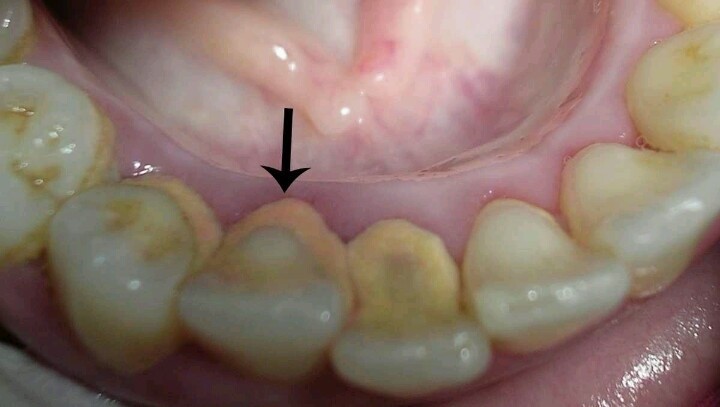

・歯肉縁上歯石:歯茎の上に形成される白っぽい歯石

・歯肉縁下歯石:歯周ポケットの中に形成される黒っぽい歯石

3-2. 歯肉縁下歯石は除去できない

歯石には歯茎の上に付着する歯肉縁上歯石と、歯茎の溝のなかにある歯肉縁下歯石の2種類があります。

家庭用のスケーラーや超音波電動歯ブラシでは、目に見える範囲の縁上歯石にはある程度対応できます。しかし、歯茎の奥深くに存在する歯肉縁下歯石の除去は困難です。

歯肉縁下歯石は硬く歯根に強固に付着しており、しかも直接確認できないため、除去には専用の器具と専門的な技術が欠かせません。